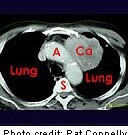

Lung-RADS Criteria Can Reduce False-Positive Result Rate

Reduction in false-positive result rate, but reduction in sensitivity also observed